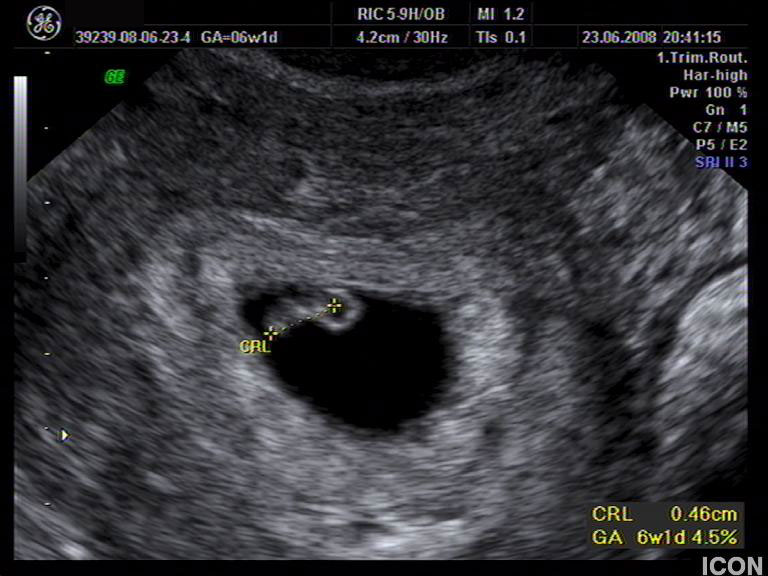

Ενδοκολπικός U/S έσω Γεννητικών Οργάνων

Αυχενική διαφάνεια

Η αυχενική διαφάνεια (ΑΔ) είναι η συλλογή υγρού στον τράχηλο του εμβρύου και συγκεκριμένα ανάμεσα στο δέρμα και στους ιστούς που καλύπτουν τη σπονδυλική στήλη.